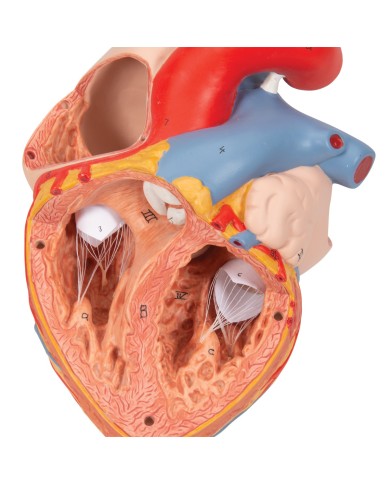

La parete anteriore del cuore è staccabile per poter vedere i ventricoli.

Modello anatomico di cuore, ingrandito 2 volte, su cavalletto

Questo modello dettagliato mostra, oltre alle strutture anatomiche del cuore, anche una parte del diaframma (base)

Realizzato in stampa 3D ad elevatissima risoluzione a colori.